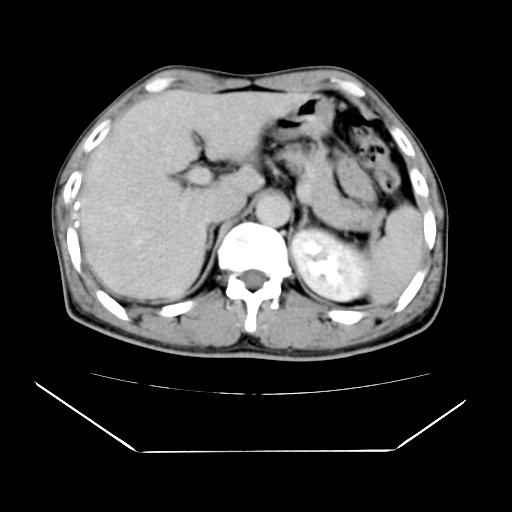

男性,55岁,外院体检afp明显升高,但b超未发现异常,否认乙肝病史。来我院ct增强。有延时扫描。

左肾囊肿.右肺中叶内侧段钙化灶.慢性胆囊炎.

延时扫描完全充填,血管瘤

肝脏右叶动脉期可见低密度影,至延迟期被充填,考虑血管瘤可能性大。

肝右叶病灶

这个不是肝右静脉吗,这么大的病灶b超不可能发现不了吧

肝6段血管瘤

血管瘤可能性大。

是肝右静脉吧

考虑肝右静脉影。